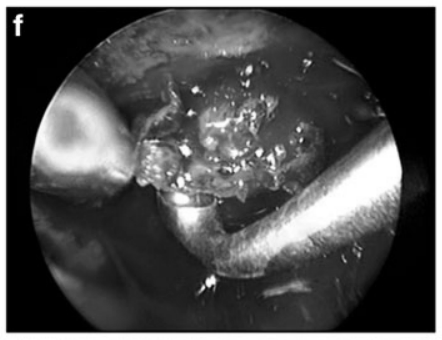

f 内镜辅助双手操作(bimanual)肿瘤切除。